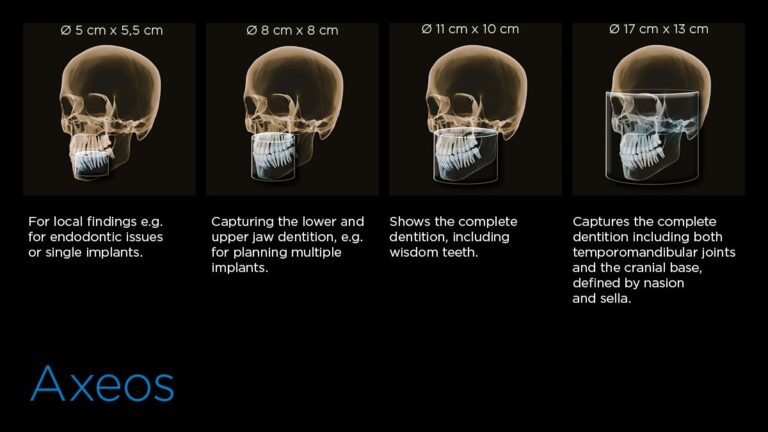

4種類のボリュームサイズ、幅広い治療への可能性

直径5cm×高さ5.5 cmから直径17cm×高さ13 cmまでのニーズに合わせたボリュームサイズ